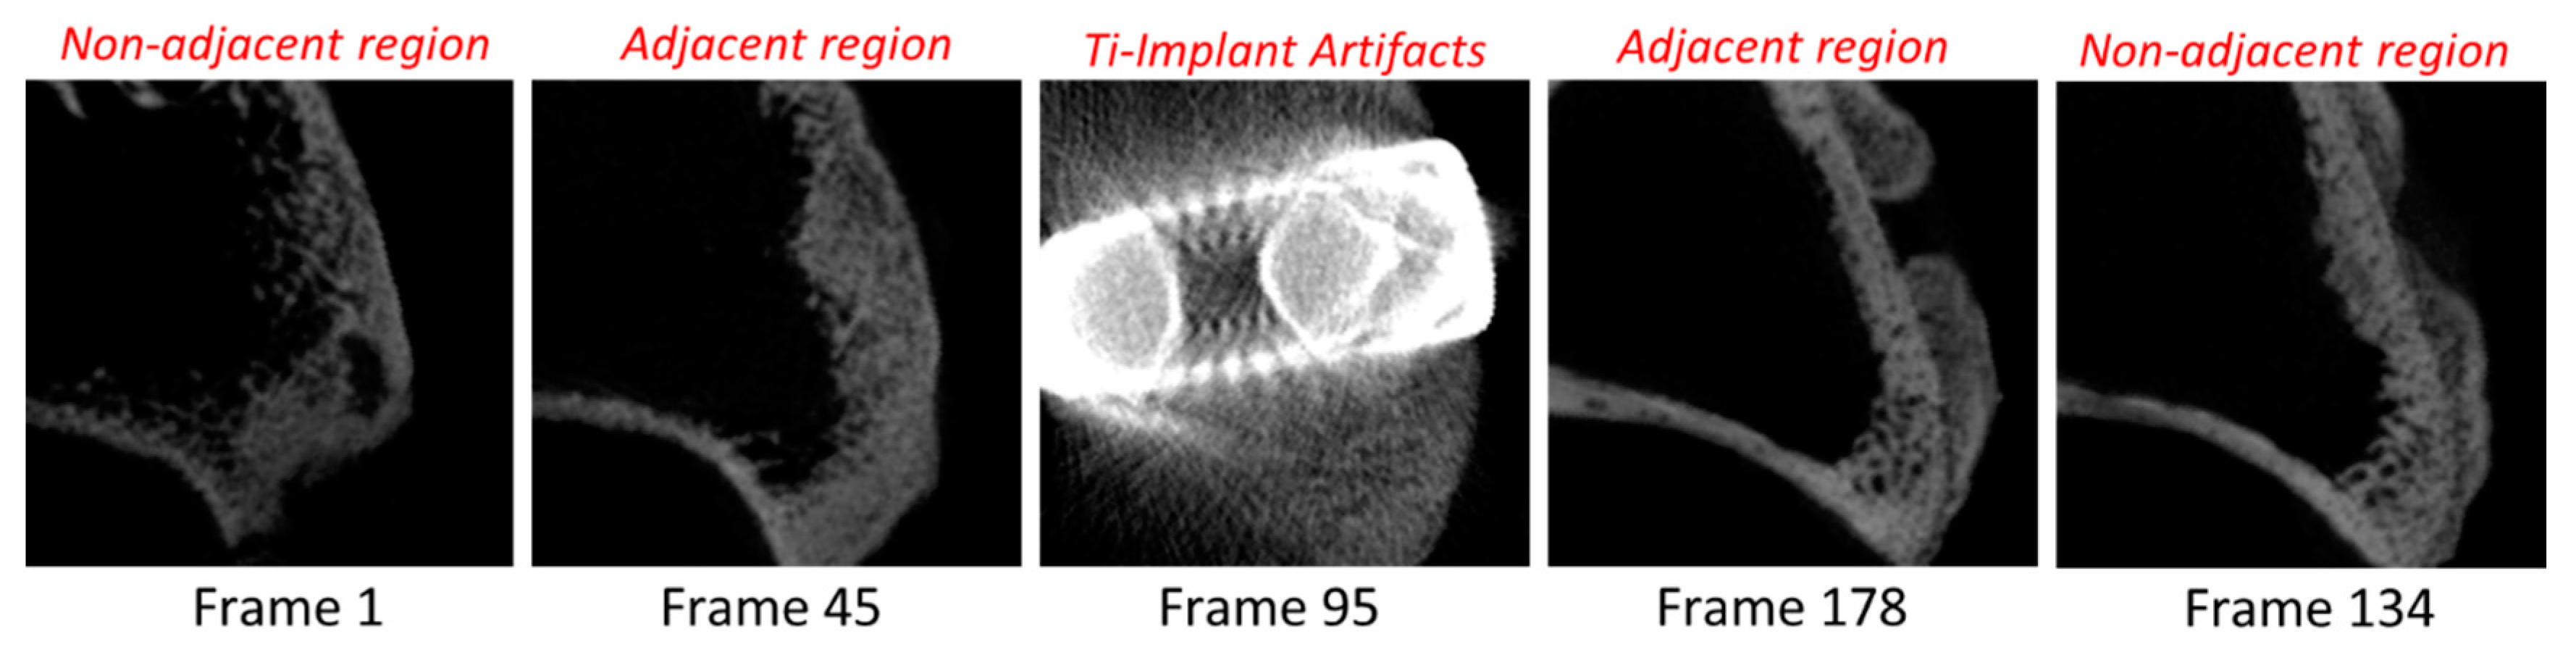

2.5. Radiological Analysis

3.3. Experimental Animal Study